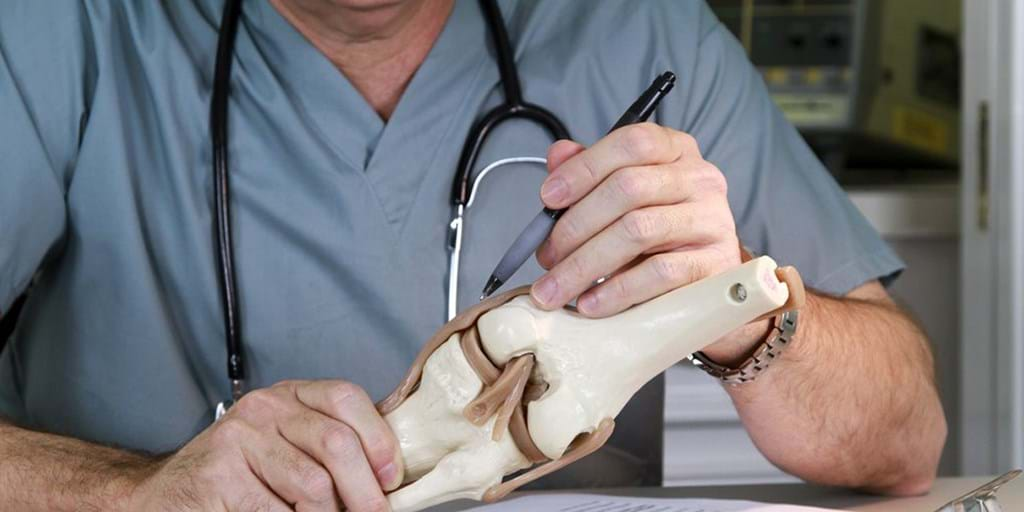

Dr. Michael Anderson, MD

Orthopedic Specialist ✅

Dr. Michael Anderson, MD

Orthopedic Specialist ✅ November 26, 2025

As an orthopedic specialist with over a decade of experience, I’ve seen firsthand the devastating impact Knee Osteoarthritis (OA) can have on my patients’ lives.